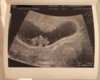

Veldig lite som skal til ja. Noen dager fra eller til gjør en stor forskjell. Hvor langt er du på vei nå?

Huff,jeg vet faktisk ikke Har jo ikke hatt ordentlig mensen siden august.

Var kjipt og ikke kunne se "noe" eller bekrefte/avkrefte exu. Men skal tilbake om en uke så kan jo ha vokst litt da.